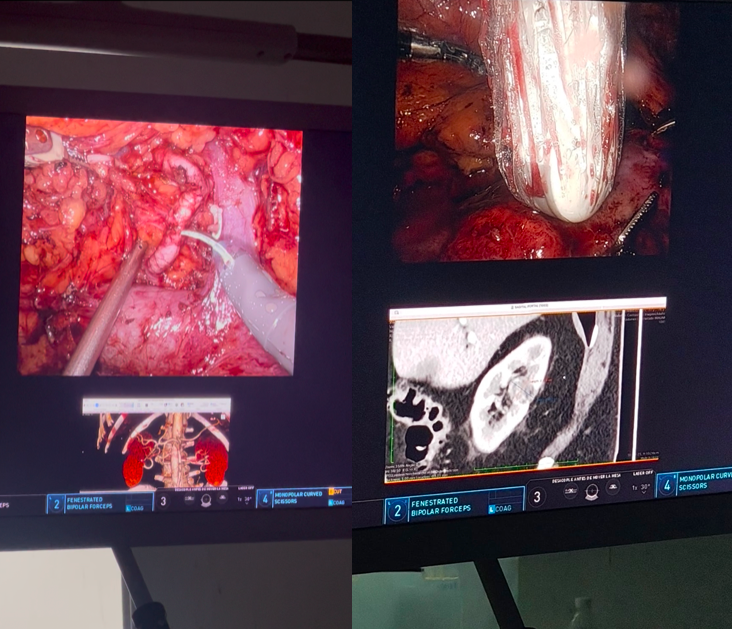

En Hospital CIMA Hermosillo, integramos nuestro Neuro EcoSistema con tecnología de última generación que mejora la precisión y seguridad en tu cirugía de columna o neurocirugía, reduciendo riegos con el soporte de imágenes en tiempo real y reduciendo tu exposición a la radiación.